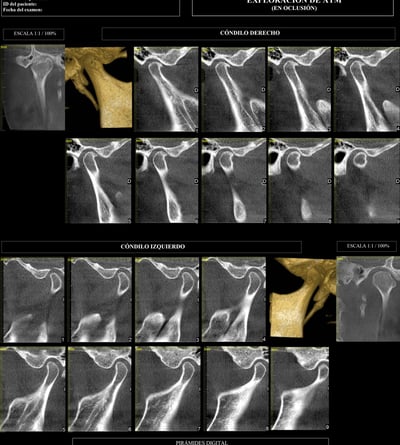

ATM

Permite detectar problemas como fracturas, desgastes, desplazamientos o anomalías en los huesos y tejidos blandos.